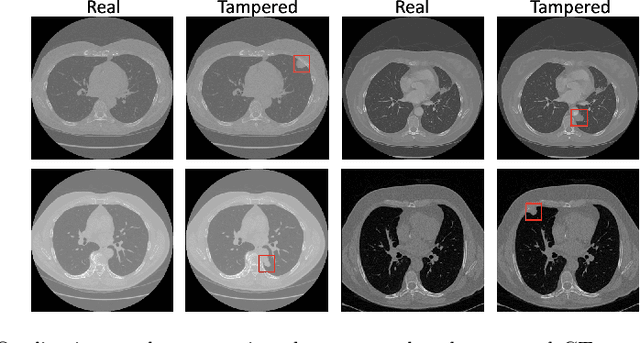

Abstract:The progress in generative models, particularly Generative Adversarial Networks (GANs), opened new possibilities for image generation but raised concerns about potential malicious uses, especially in sensitive areas like medical imaging. This study introduces MITS-GAN, a novel approach to prevent tampering in medical images, with a specific focus on CT scans. The approach disrupts the output of the attacker's CT-GAN architecture by introducing imperceptible but yet precise perturbations. Specifically, the proposed approach involves the introduction of appropriate Gaussian noise to the input as a protective measure against various attacks. Our method aims to enhance tamper resistance, comparing favorably to existing techniques. Experimental results on a CT scan dataset demonstrate MITS-GAN's superior performance, emphasizing its ability to generate tamper-resistant images with negligible artifacts. As image tampering in medical domains poses life-threatening risks, our proactive approach contributes to the responsible and ethical use of generative models. This work provides a foundation for future research in countering cyber threats in medical imaging. Models and codes are publicly available at the following link \url{https://iplab.dmi.unict.it/MITS-GAN-2024/}.